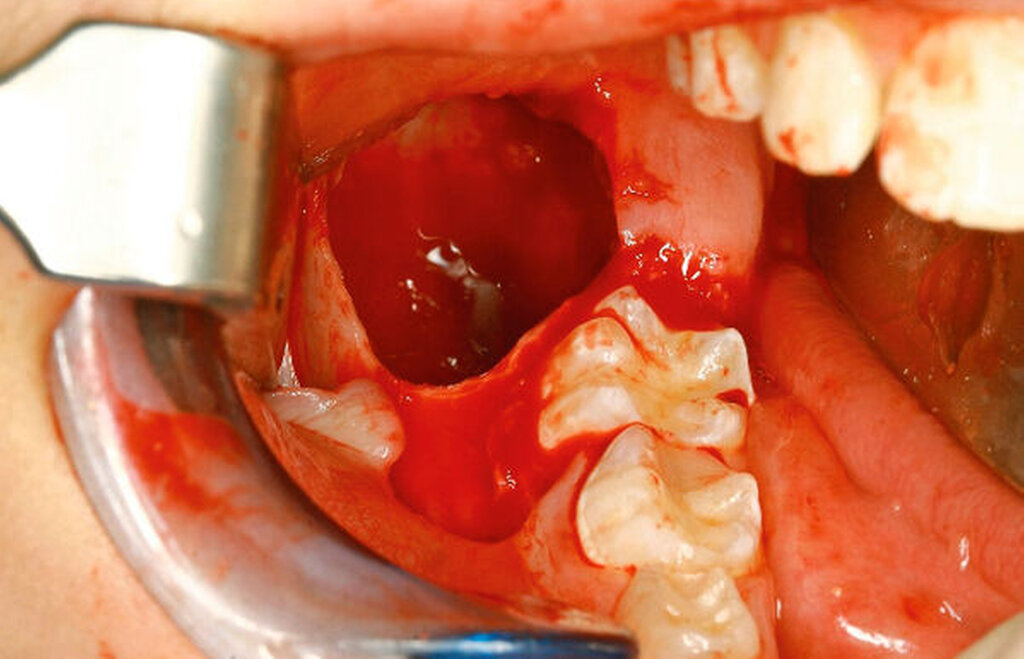

Unter der Vollnarkose erfolgte zunächst eine gründliche intraorale Inspektion, wobei sich im Bereich des Kieferwinkels rechts die knöcherne Ausbuchtung nach vestibulär deutlich darstellte (Abbildung 2). Es folgten eine Infiltrationsanästhesie im Bereich des rechten Kieferwinkels und anschließend eine marginale Inzision regio 85–46 mit Fortführung nach distal-vestibulär sowie anteriorer Entlastung. Nach Bildung eines Mukoperiostlappens wurde die Raumforderung in regio 47 mittels Osteotomie unter Schutz des N. lingualis dargestellt.

Hier zeigte sich zunächst eine bindegewebige Hülle (Abbildung 3), von der zusammen mit dem darunter liegenden Gewebe eine Probe zur intraoperativen histopathologischen Schnellschnittdiagnostik eingesendet wurde. Nach Entfernung der bindegewebigen Hülle im Bereich der Osteotomie folgte die Darstellung der sich darunter befindlichen festen Raumforderung. Diese konnte in toto enukleiert werden (Abbildungen 4 und 5). Darunter zeigte sich der retinierte und verlagerte Zahn 47. Dieser konnte im Anschluss problemlos mittels Hebel nach Bein gelöst und geborgen werden (Abbildung 6).